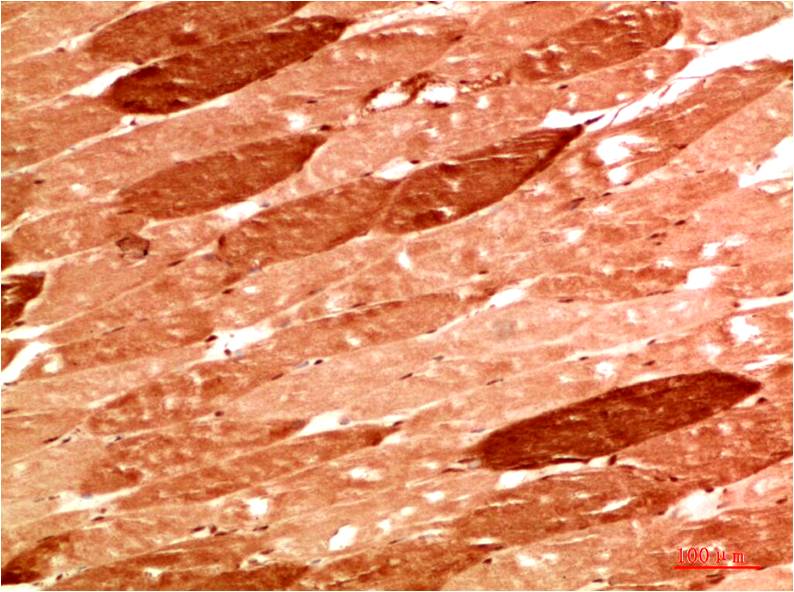

STAT1 Rabbit Polyclonal Antibody

Applications :WB, IHC

| Recommended dilutions: | WB:1:1,000-2,000 IHC:1:200-500 |